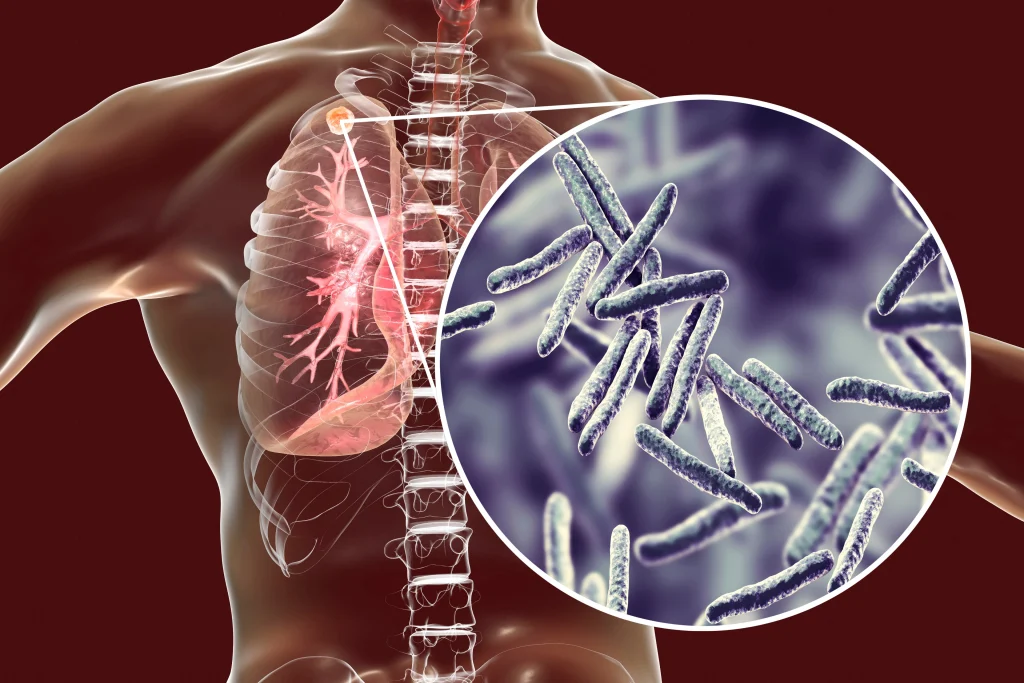

نن د مارچ ۲۴مه د نري رنځ نړیواله ورځ ده. په افغانستان کې د دې ناروغۍ د مخنیوي لپاره د څه باندې ۵۰ زره کسانو درملنه شوې او هڅې لا هم په چټکۍ سره دوام لري.

د مارچ ۲۴مه نېټه په ټوله نړۍ کې د نري رنځ نړیواله ورځ ده، دا ورځ هر کال د دې وژونکې ناروغۍ د له منځه وړلو او د مخنیوي د هڅو په اړه د عامه پوهاوي لوړولو لپاره نمانځل کېږي.

د اسلامي امارت د عامې روغتیا وزارت تېر کال اعلان وکړ چې هر کال ۷۵ زره افغانان په دې ناروغۍ اخته کېږي، چې له دې ډلې ۱۰ زره یې مري. له همدې امله په هېواد کې د نري رنځ نړیواله ورځ د عامه پوهاوي د یوه مهم فرصت په توګه خورا زیات ارزښت لري.